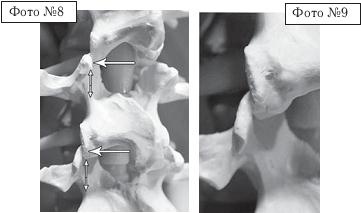

На фото № 6 макета позвоночника наблюдается смещение (подвывих) суставных поверхностей дугоотростчатых суставов. На фото № 7 наблюдается смещение (подвывих) суставных поверхностей дугоотростчатого сустава (увеличенный вариант). ![]() На фото № 8 макета позвоночника наблюдается перерастяжение дугоотростчатых суставов вследствие вытяжения. На фото № 9 наблюдается перерастяжение дугоотростчатого сустава (увеличенный вариант). ![]() Фото № 10 На фото № 10 макета позвоночника наблюдается нормальное взаимоотношение суставных поверхностей дугоотростчатых суставов, в норме высота межпозвонкового диска и межпозвонковых отверстий. ![]() Фото № 11 На фото № 11 макета позвоночника наблюдается смещение (подвывих) суставных поверхностей дугоотростчатых суставов. Подобное смещение, как правило, происходит вследствие развития дегенеративно-дистрофических процессов в межпозвонковом диске. При этом уменьшается высота диска, сужается просвет фораминального отверстия (межпозвонкового), что может способствовать ущемлению спинномозговых корешков (нервов) и сосудов. ![]() Фото № 12 На фото № 12 макета позвоночника наблюдается перерастяжение дугоотростчатого сустава вследствие вытяжения, расширение фораминального отверстия, а также растяжение задних отделов фиброзного кольца межпозвонкового диска и сближение вентральных (передних) отделов тел позвонков. Это приводит межпозвонковый диск в клиновидное состояние, что способствует выталкиванию содержимого межпозвонкового диска из передних его отделов в задние. |